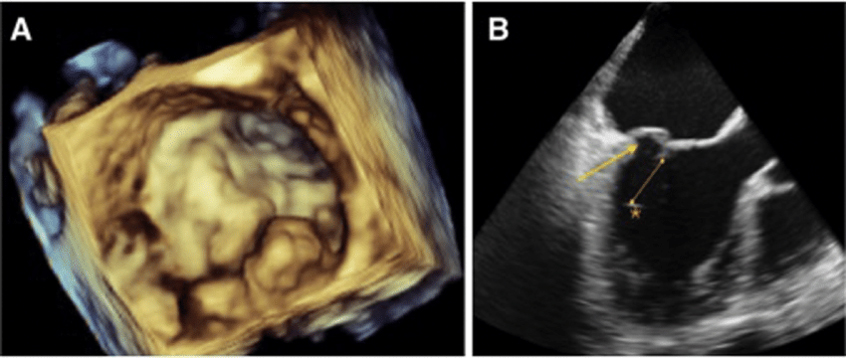

1. Transthoracic echocardiogram (TTE): This is the most common type of echocardiogram. It involves placing the transducer on the chest wall (over the heart area) to obtain images of the heart's structures and blood flow.

2. Transesophageal echocardiogram (TEE): In this type of echocardiogram, the transducer is attached to the end of a flexible tube (probe) that is passed through the esophagus. This allows for more detailed images of the heart since the esophagus is located directly behind the heart.